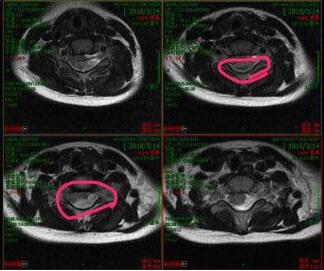

CT片显示,琦琦椎管内有出血,压迫了神经,导致他出现瘫痪症状。武汉儿童医院神经外科主任杜浩主刀为他做了手术,清除血块,之后给与对症治疗。一家人后怕不已,好在琦琦的病情逐渐好转。 26日,琦琦基本恢复正常,康复出院。